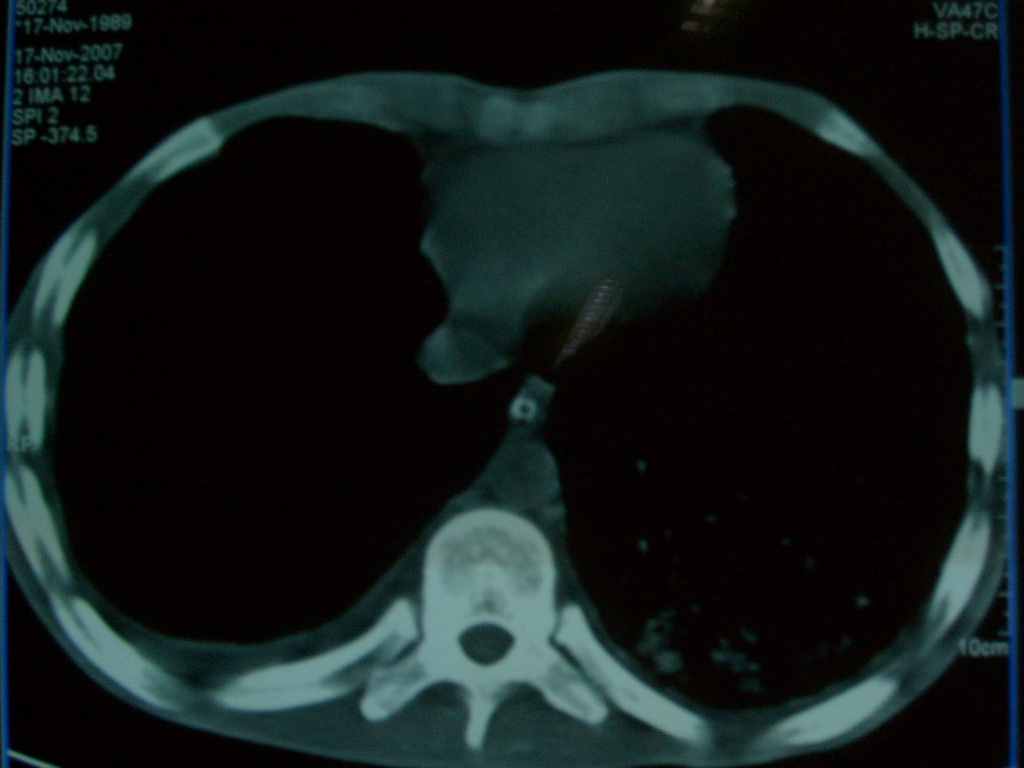

标题: CT10510:男.18岁,咳嗽咳痰两月.(有病理) [打印本页]

标题: CT10510:男.18岁,咳嗽咳痰两月.(有病理)

双肺布满大片状实变及网格状结节影,内参杂大小不等的气囊及空气支气管征,心脏增大。考虑:1 全身结缔组织疾病—系统性红斑狼仓?2 肺泡蛋白沉积症合并感染!

双肺布满大片状实变及网格状结节影,内参杂大小不等的气囊及空气支气管征,双侧胸膜腔少量积液,双下肺近膈面透亮度尚可,病人较年轻,病变较重(不知为什么上胃管?)考虑:1.胶原病肺部改变,2.组织细胞病x。结合实验室检查。

首先考虑组织细胞x病。两肺中上肺野多发囊腔,中下肺野内见多发小结节,并可见肺间质增厚。患者是男性,年龄较小。胶原性病变比较多见的类风湿、系统性红斑狼疮和硬皮病临床和影像均不是很支持,类风湿和系统性红斑狼疮的肺部表现最常见的是胸腔积液,硬皮病可见食管的扩张。

肺内多发斑片状、结节状、融合大片状及网格状影,多发薄壁空腔影,胸膜肥厚,纵隔、气管右移,考虑ⅲ型肺结核,多发空洞,继发肺间质纤维化。

双肺结核并播散.患者以肠梗阻入院,手术为肠结核.术后咳嗽做ct检查.